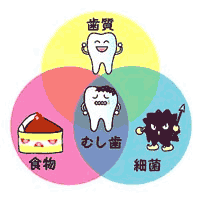

虫歯予防には「ハミガキ」とざっくり思っている方が多いのではないでしょうか。もちろんハミガキは必要不可欠です。しかし実はいろいろな要因が重なった時に虫歯は作られます。(1)歯質、(2)細菌、(3)食物(糖質)。この3つの要因が重なり停滞時間が長いほど作られやすくなります。ということはこの3つの要素を予防・強化することで虫歯は防げるということになります。

(1)歯質…歯の酸への抵抗力を強化する。フッ素を歯に取り込むことが効果的です。フッ素塗布、フッ素入り歯磨剤・洗口液が有効です。

(2)細菌…口の中には誰でも虫歯菌(ミュータンス菌)が生息しています。これは糖分が大好きでプラークを作り出します。そこで、

(3)食物(糖質)←摂取の改善です。砂糖の多く含む食物を口の中に長時間停滞させないことが大事になります。だらだら食い・過度な間食・粘着性の多い食べ物は虫歯を作りやすくしてしまうので控えるようにしましょう。

虫歯にならないために様々な生活習慣に気を付けて虫歯予防していきましょう。フッ素塗布は専門的ケアとなりご自身での細部にわたるブラッシングは難しいと思われます。そこで定期的な検診をお勧めします^^